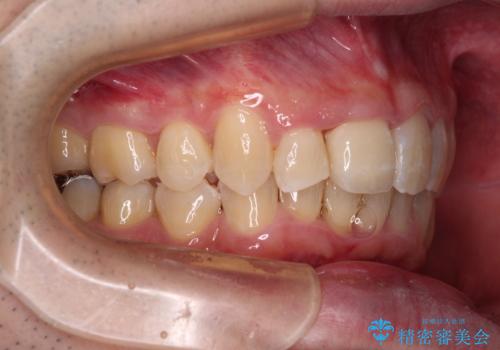

矯正治療後にはオーダーメイドタイプのオールセラミッククラウンを装着し、自然な口元に仕上がりました。

通常では速やかにオールセラミッククラウンにて補綴治療を行うのですが、デコボコしている歯列も気になっていたため、事前に矯正治療を行うこととしました。

上顎歯列の叢生が著しかったため、上顎左右第一小臼歯2本を抜歯し、目立たないワイヤー装置にて治療を進めることとしました。